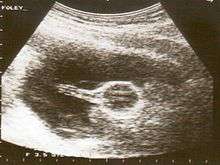

Cervical

A Foley catheter can also be used to ripen the cervix during induction of labor. When used for this purpose, the procedure is called extra-amniotic saline infusion (EASI).[2] In this procedure, the balloon is inserted behind the cervical wall and inflated, such for example with 30 mL per hour.[2] The remaining length of the catheter is pulled slightly taut, and taped to the inside of the woman's leg. The inflated balloon applies pressure to the cervix, as the baby's head would prior to labour, causing it to dilate. As the cervix dilates over time, the catheter is readjusted to again be slightly taut, and re-taped to maintain pressure on the cervix. When the cervix has dilated sufficiently, the catheter simply drops out.[3]